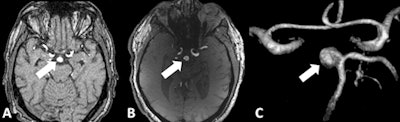

Image A shows 1.5-tesla TOF MRA of a 55-year-old patient with an unruptured basilar aneurysm (arrow). Image B is a corresponding 7-tesla TOF MRA and image C is a maximum intensity projection image. 7-tesla MRA produced superior delineation of the aneurysm with enhanced image sharpness and clarity. Images courtesy of Dr. Lale Umutlu."In our study, we were able to improve the spatial resolution to a minimum voxel size of 0.2 x 0.2 x 0.4 mm3 at 7 tesla, instead of 0.35 x 0.35 x 0.7 mm3 at 1.5 tesla," Umutlu explained. "Based on this superior spatial resolution, as well the improved vessel-to-tissue contrast, 7-tesla TOF MRA allowed for a significantly improved delineation of the intracranial aneurysms."